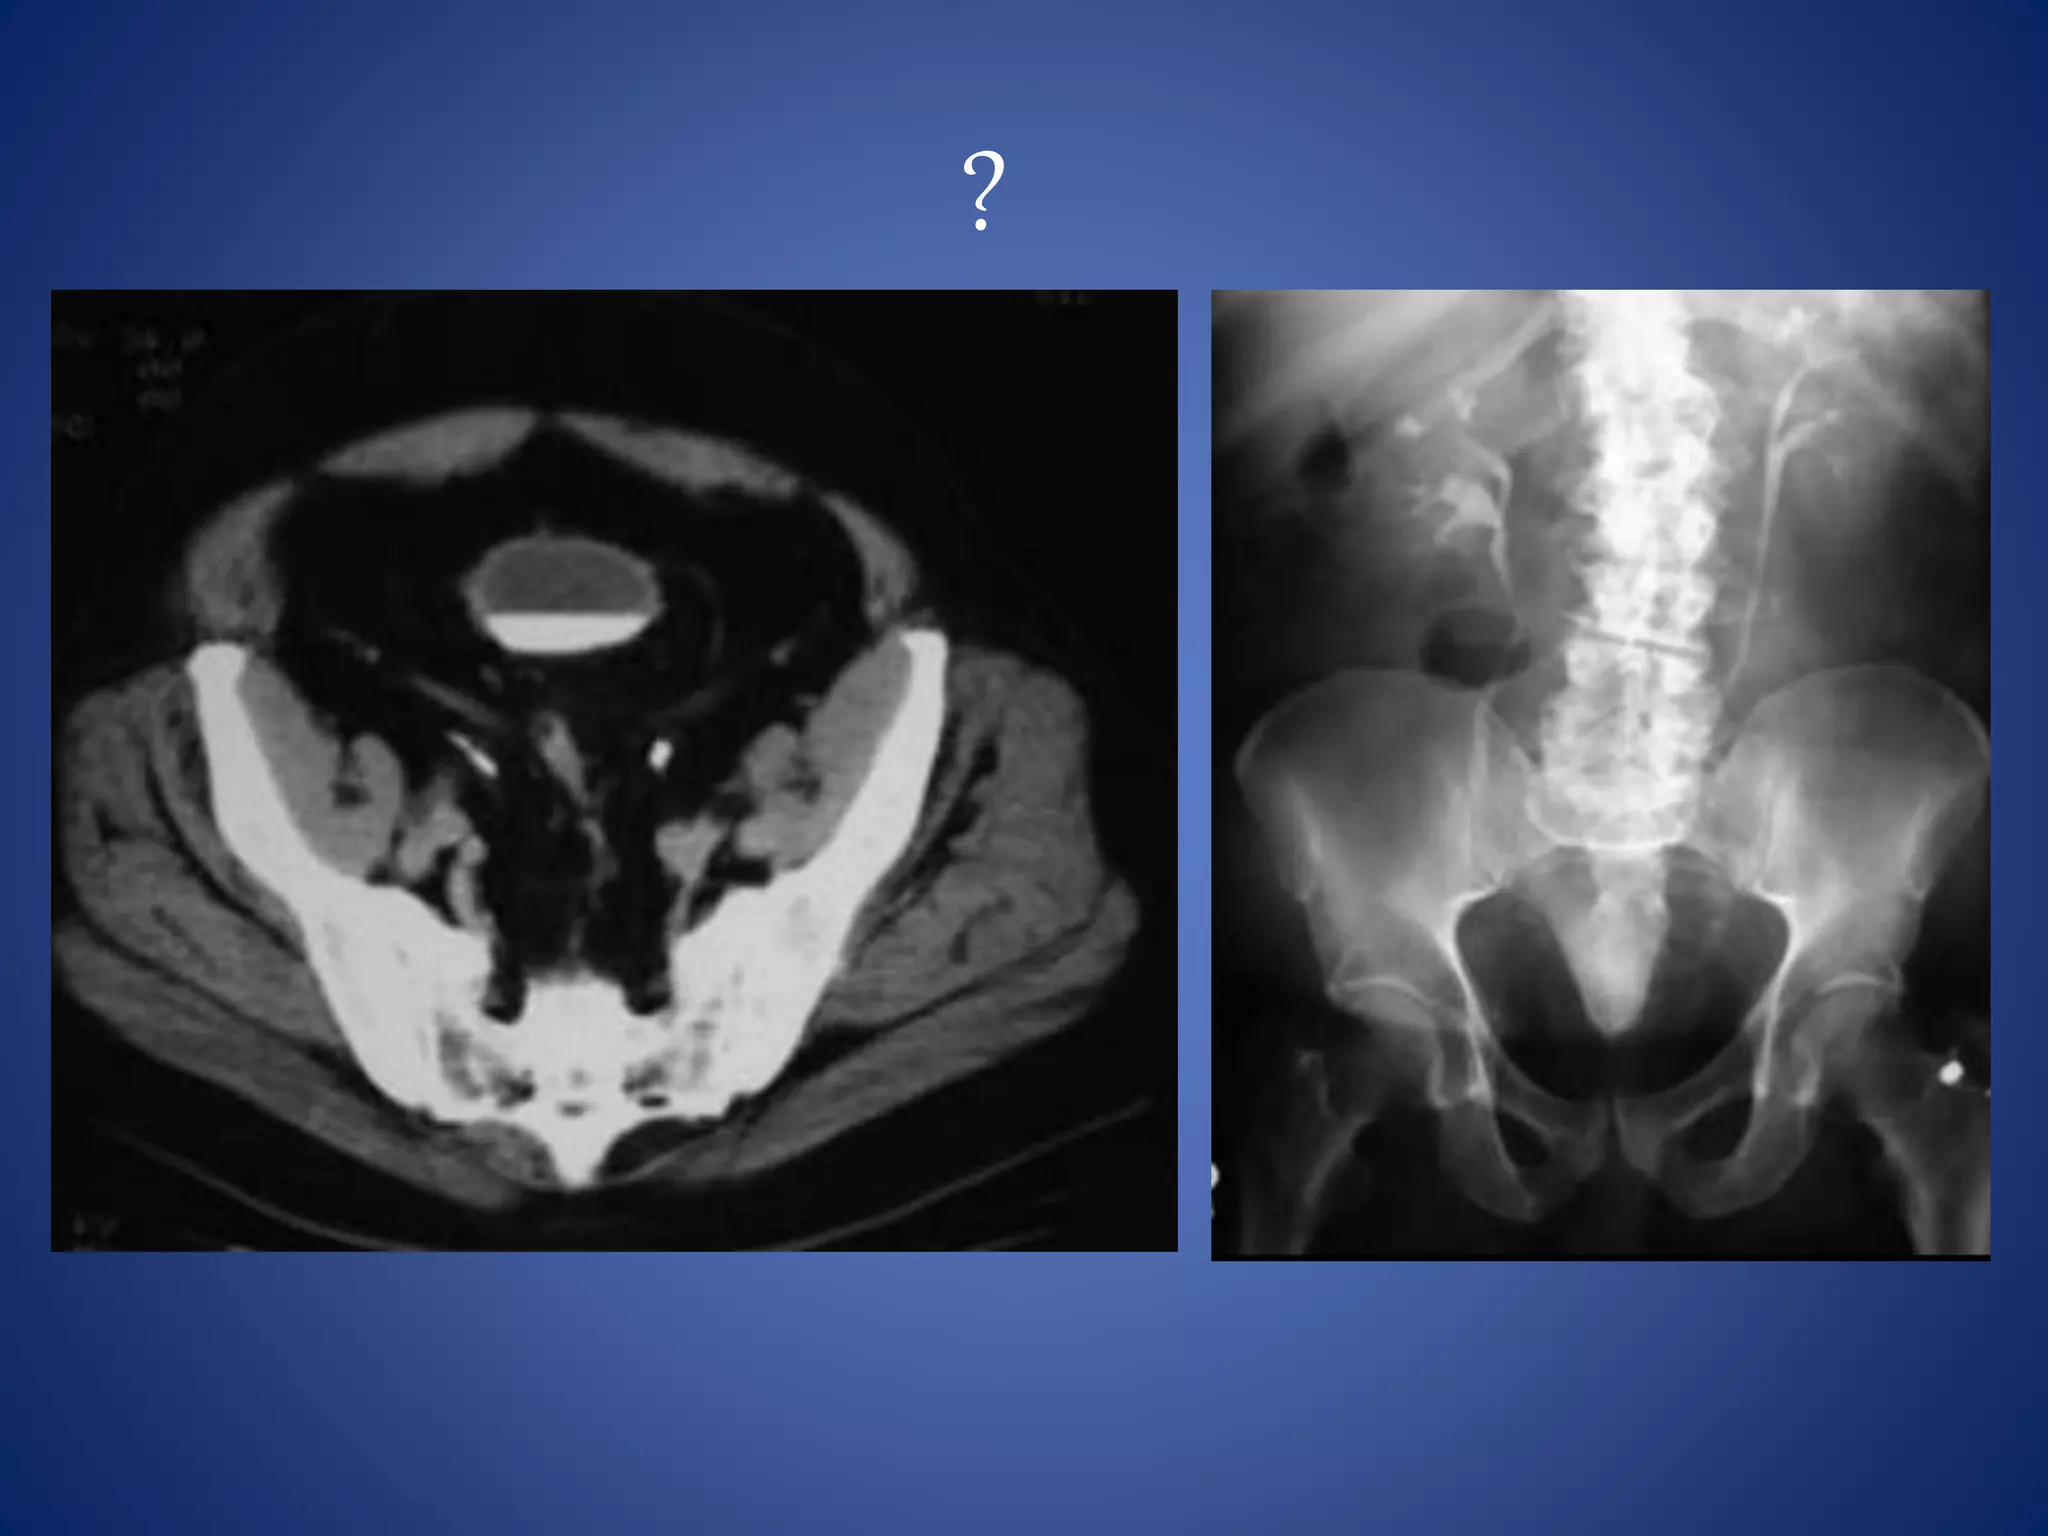

• #72 PELVIC LIPOMATOSIS --- IVU demonstrating elevation and lateral compression of bladder. CT of pelvis with contrast demonstrating increased fat surrounding the bladder causing lateral compression with elevation of the bladder floor